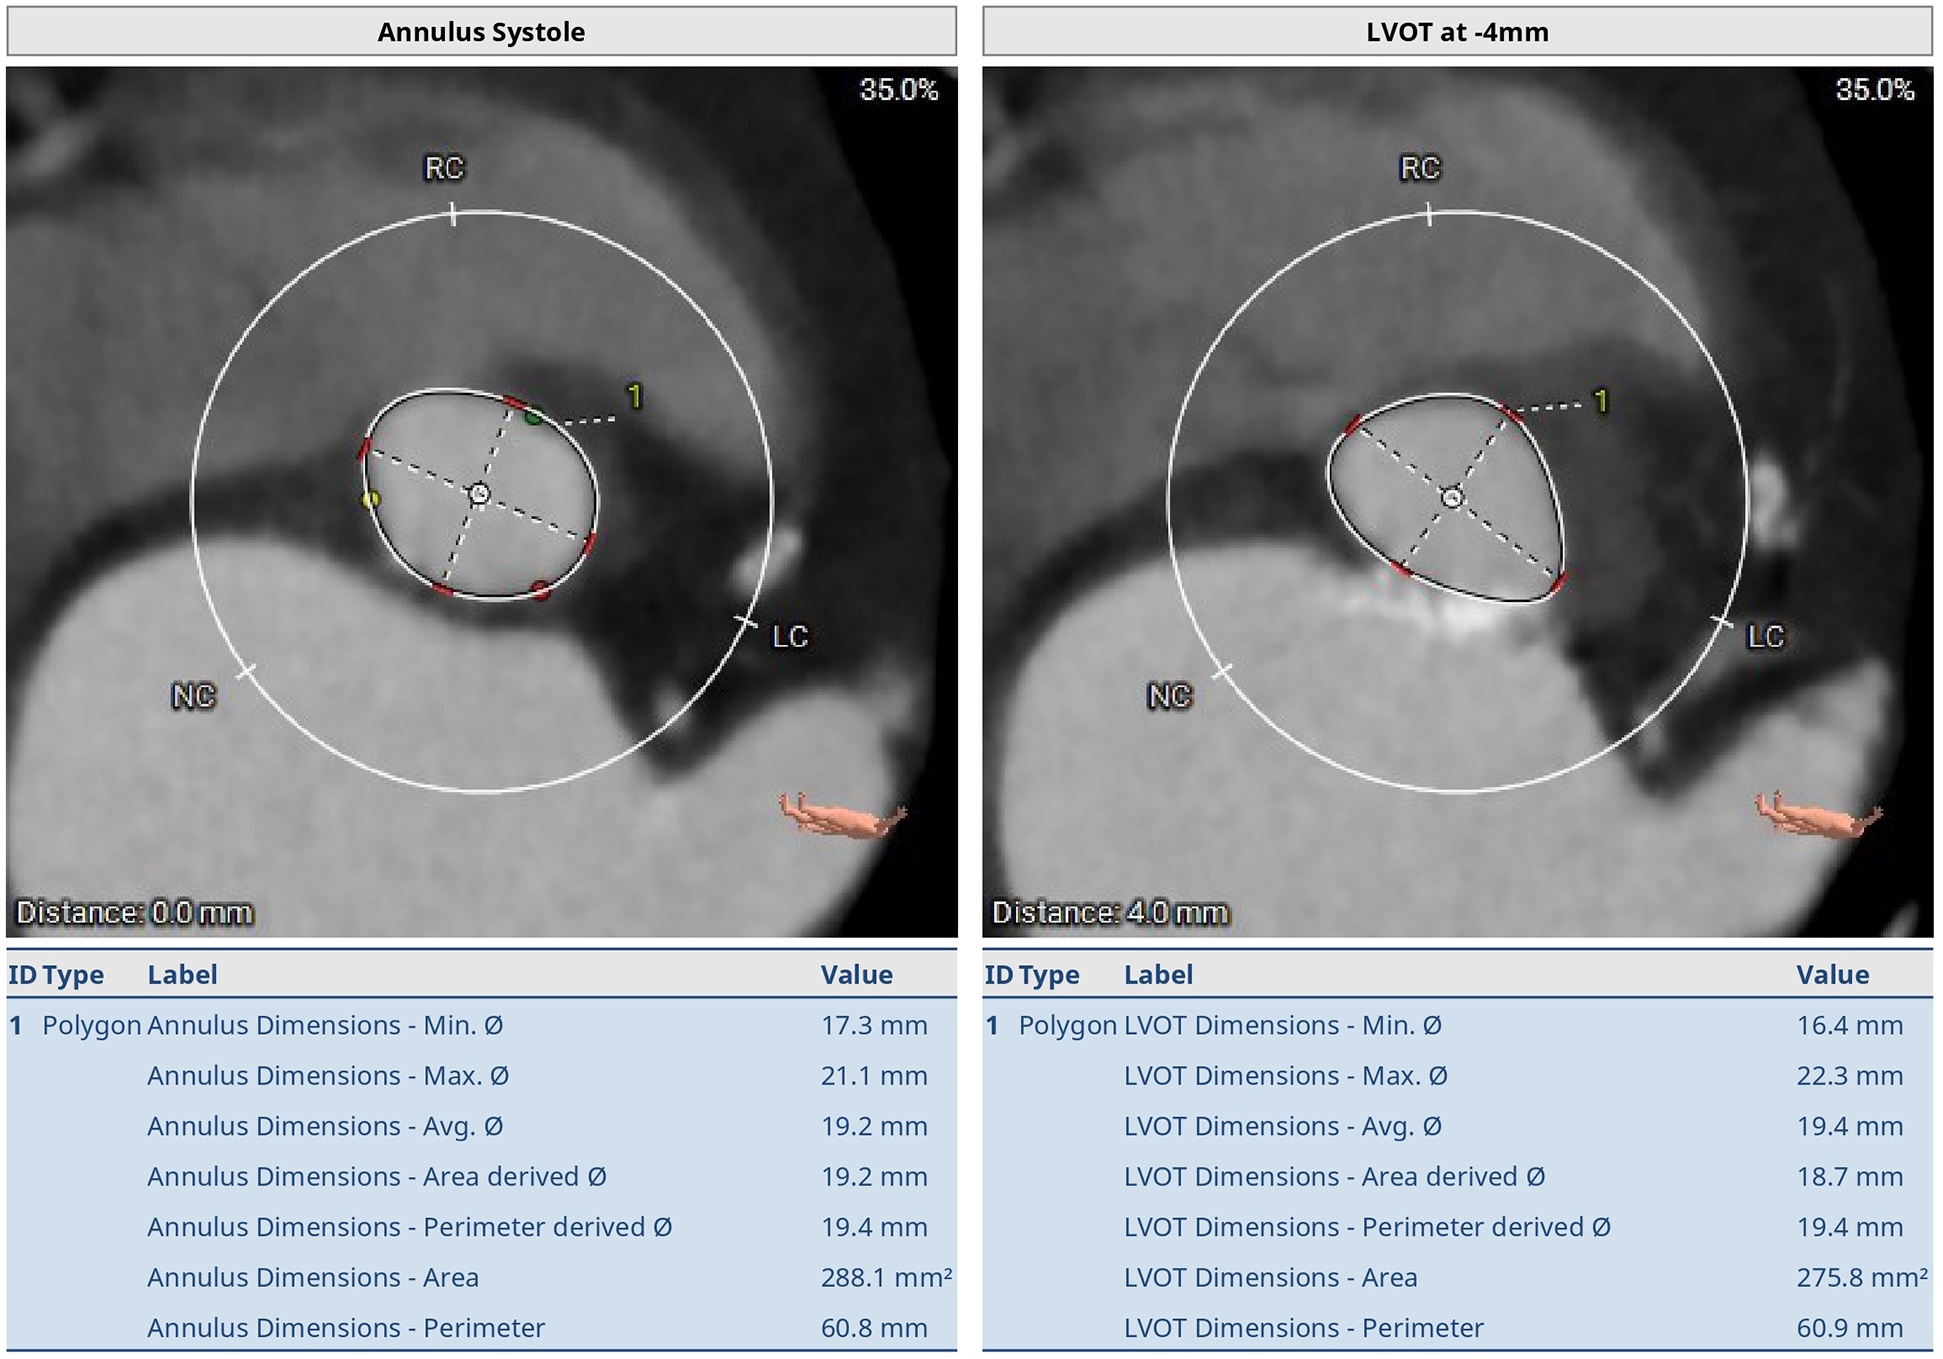

Figure 2

Preoperative thoraco-abdominal CT images showing the annular measurements at systole. The aortic annulus perimeter was 60.8 mm (minor annulus diameter 17.3 mm, major annulus diameter 21.1 mm) and the area was 288.1 mm2. The LVOT perimeter was 60.9 mm (minor annulus diameter 16.4 mm, major annulus diameter 22.3 mm) and the area was 275.8 mm2.

Transthoracic echocardiography was carried out, which showed a thickened, calcified, and severely stenotic aortic valve, measuring 0.7 cm2 (normal range 2.5–4.5 cm2), and peak and mean pressure gradients of 55 and 40 mmHg (normal range <5 mmHg). The Vmax of the aortic valve was 3.8 m/s (normal range <2 m/s). Preoperative thoraco-abdominal computed tomography angiography (CTA) showed an aortic annulus perimeter of 55.4 mm, ventricular outflow tract of 13.5 mm, short-axis diameter of 15.1 mm, and long-axis diameter of 20.2 mm at the annulus. Sinus width was 25 mm, diameter of the sinotubular junction was 17.8 mm, the ascending aorta was 24 mm wide, and sinus height was 14.3 mm. The distance to the first coronary (right) was 16.1 mm. The aortic annulus perimeter was 60.8 mm (minor annulus diameter 17.3 mm, major annulus diameter 21.1 mm) and the area was 288.1 mm2. The LVOT perimeter was 60.9 mm (minor annulus diameter 16.4 mm, major annulus diameter 22.3 mm) and the derived area was 275.8 mm2 (Figures 1–3).